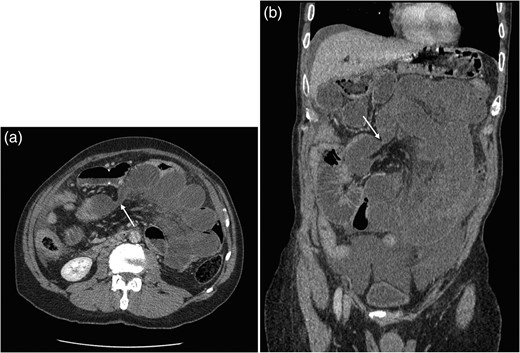

Computed tomography (Fig. 1) demonstrated a closed loop small bowel obstruction involving almost all of the jejunal loops with mesenteric venous congestion suggesting impending ischaemia. The transition point was posterior to the Roux loop.

(a and b) Axial and coronal CT images showing obstruction of small bowel with transition point within Petersen's space (arrow).